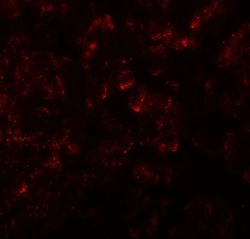

Supportive validation

- Submitted by

- GeneTex (provider)

- Main image

- Experimental details

- Immunofluorescence of KIRREL2 in human pancreas tissue with KIRREL2 antibody at 20 μg/ml.